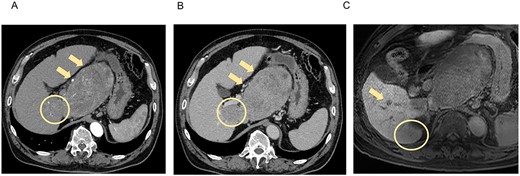

Postoperatively, tumor marker concentrations were normalized promptly after surgery (Fig. 4). The patient is currently alive at 12 months postoperatively without recurrence.

Treatment timeline with the pre- and postoperative serum AFP and PIVKA-II concentrations.

The effectiveness of treatment for HCC is evaluated by CT and MRI with reference to the modified RECIST [8]. In addition to imaging evaluation, follow-up of AFP and PIVKA-II concentrations is also reported to be useful for measuring treatment efficacy [9, 10]. Shindoh et al. [11] reported that a decrease in PIVKA-II concentration from baseline is a strong predictor of successful R0 resection after LEN treatment. In the present case, gradual decreases in AFP and PIVKA-II concentrations were observed over the course of treatment, which might help in the treatment evaluation of LEN plus TACE. Patients receiving LEN should be followed up closely by measuring tumor markers and performing imaging examinations.